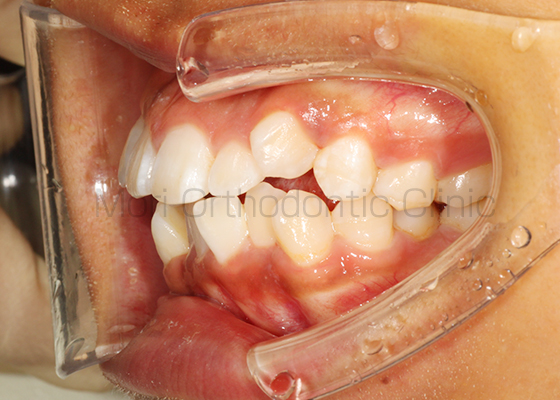

術前

術後

| 主訴 | 歯並び、八重歯 |

|---|---|

| 診断名 | AngleⅡ級叢生 |

| 年齢 | 30歳2か月 |

| 治療装置 | Multi-Bracket(表側矯正)、CARRIERE DISTALIZER |

| 抜歯部位 | 14,24,35,45 |

| 治療期間 | 2年1か月 |

| 治療費 | 825,120円(税込) |

| リスク・副作用 | 矯正治療による歯の移動に伴う痛み、歯根吸収、歯肉退縮、虫歯 |